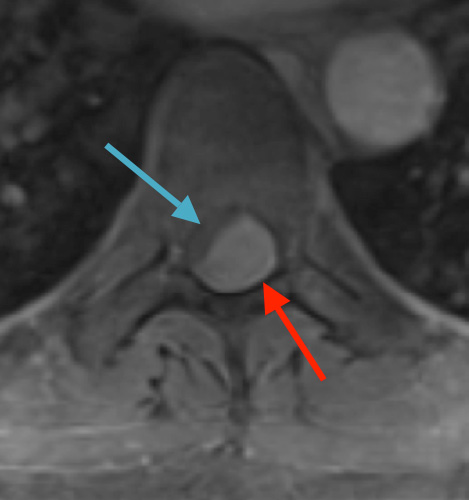

Postoperative MRI T1w demonstrating interval resection with cord re-expansion (blue arrow)

Postoperative MRI T2 illustrating the restoration of CSF surrounding the cord (blue arrow)

Pathology came back as Atypical Meningioma, WHO grade 2. Postoperative MRI showed a gross total resection without residual tumor, and appropriate spinal cord re-expansion. On her most recent follow-up at 6 weeks, she was very pleased with the results from the surgery. She reports resolution of her preoperative thoracic back and radicular pain, and great improvement with her ability to ambulate and overall function. It is demonstrated by her interval VAS of 2/10, and ODI of 23/100. She is expected to continue improving with time and therapy. Follow-up plan is to observe with radiographic surveillance.